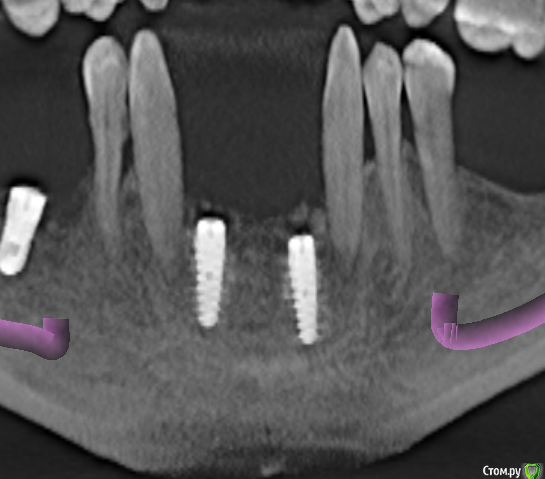

samanta66 Опубликовано 22 марта, 2015 Поделиться Опубликовано 22 марта, 2015 Добрый день.Срочно нужна консультация специалистов. Импланты (передние) поставлены более 9 месяцев назад. Казалось, вросли основательно. На этапе протезирования, когда уже полностью был готов протез, ортопед сказал, что имплант расшатался, послал к хирургу. Сделали снимок, на котором увидели, что имплант стоит не вертикально (как было изначально). 1. Как-то можно исправлять ситуацию? Хирург предлагает убирать этот имплант и через время ставить новый. У меня сомнения: не повторится ли ситуация ?2. Почему имплант расшатался? Во время многочисленных примерок ортопед прилагал немалые усилия, так как что-то там не влезало по моим ощущениям. Можно свидетельствовать, что ортопед своими действиями "свернул" имплант ? Он отказывается переделывать бесплатно свою работу. Для сравнения предлагаю 2 КТ (за октябрь и март). октябрь март крупнее Ссылка на комментарий

diesel87 Опубликовано 22 марта, 2015 Поделиться Опубликовано 22 марта, 2015 стоит судя кт он так же как его и ставили. только видимо нет кости вестибулярно. скорее всего перестановка Ссылка на комментарий

Mane Опубликовано 22 марта, 2015 Поделиться Опубликовано 22 марта, 2015 Ортопед тут не причем. Правильно установленный имплантат в необходимоеиколичество кости особенно в вашей области челюсти не то что руками, инструментом практически не возможно открутить/свернуть. Смею предположить что установлен имплант с нареканиями. На месте ортопеда - правильная позиция. Почему он должен быть громоотводом и расплачиваться за недочеты других специалистов. 8 Ссылка на комментарий